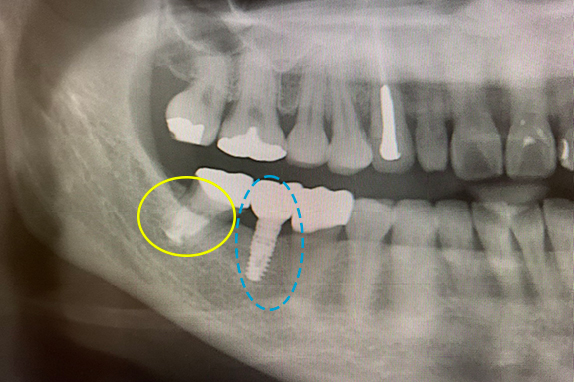

1. マイクロエンド+インプラント治療術前

2. マイクロエンド+インプラント治療術後

• 主訴

痛くて噛めない(50代女性)

• 回数期間

6回 約3ヶ月

• 治療法

マイクロエンド+インプラント

• 治療費用

約65万円(税抜)

右の奥歯が痛くて噛めないという主訴で来院。7番をマイクロエンドで改善し、6番にインプラントを埋入したケースです。

<リスク・副作用>

術後は顔面の腫脹に加え、青あざができる場合があります。過度な衝撃や咬合を加えると補綴物の破折、脱落の可能性があります。